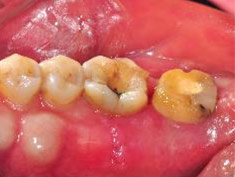

牙周初診時患者之口內觀。口內明顯牙菌斑及牙結石堆積。全口嚴重牙齦紅腫。治療前X光片。#37的近心側有較深的骨內缺損,剩餘齒槽骨高度只有20%。

第一階段牙周基本治療後,牙齦發炎狀況明顯獲得改善。